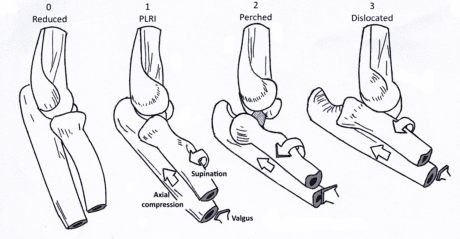

Sværhedsgraden af PLRI kan inddeles i tre faser(Camp et al. 2017):

1. Løsrivelse eller overrivning af LCL-komplekset

2. Siddende forvridning: Større anterior forskydning, progression af vævsforstyrrelser anteriort og posteriort omkring albuen til den mediale side

3. Fuld forvridning: Vævsforstyrrelse involverer det mediale kollaterale ligament, som typisk er skrællet af knoglen